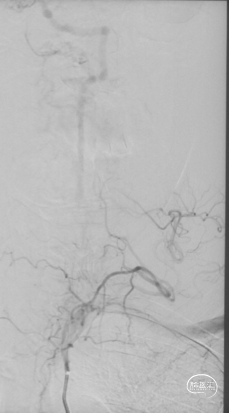

术后情况

术后复查

复查头颅MRI未见新发梗死